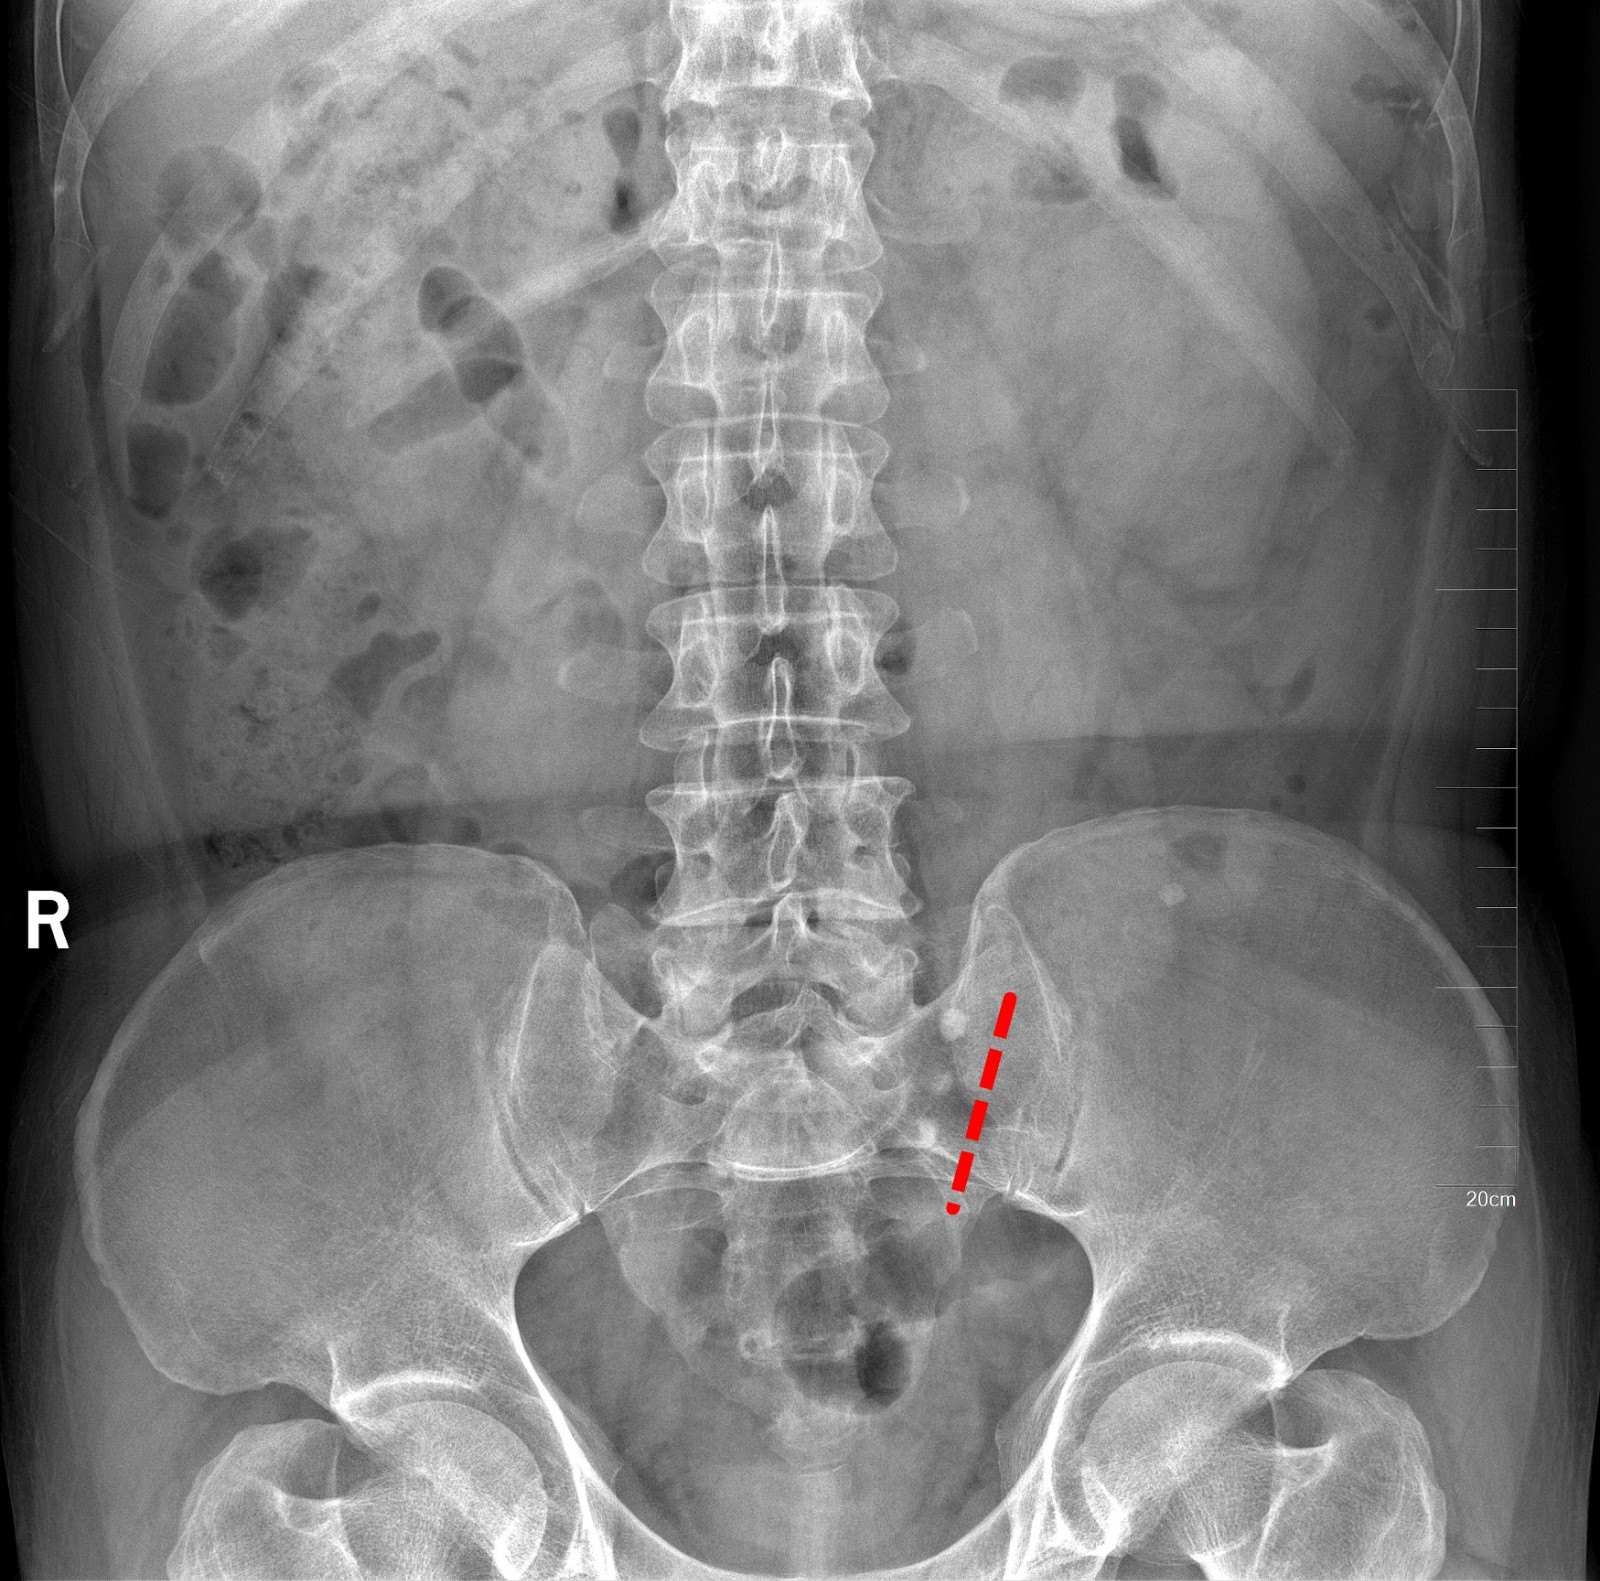

CT检查提示:双侧肾脏重度积水双侧输尿管中段结石 双侧输尿管上段积水扩张

入院后行双侧经皮肾穿刺造瘘术,保护肾功能,十天后Cr下降至236umol/L,顺行造影检查发现双侧输尿管迂曲扩张明显,双侧输尿管结石完全梗阻,造影剂无法进入膀胱。